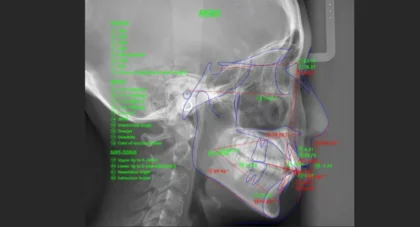

顎のズレまで精密に診断、当院独自のデジタル診断

矯正治療は、歯並びを整えるだけでは本当の改善にはつながりません。顎の位置や噛み合わせ、横顔とのバランスまで正確に把握することが、美しい口元と健やかな噛み合わせを実現する鍵です。

表参道AK歯科・矯正歯科では、AIを活用した独自のデジタル診断を導入しており、矯正治療のインストラクターとして歯科医師に指導を行う経験豊富な歯科医師が担当します。診断後の精密検査により、矯正だけでなく顎関節や顎のズレまで含めた総合的な診断を行い、その結果をもとに最適な治療計画を立案します。

当院のデジタル診断は、単なる評価にとどまらず、治療方針の策定に直結。顎のズレや噛み合わせの状態を正確に把握し、咀嚼や発音などの機能面まで考慮した、見た目と機能の両立を目指す包括的な治療をご提供いたします。